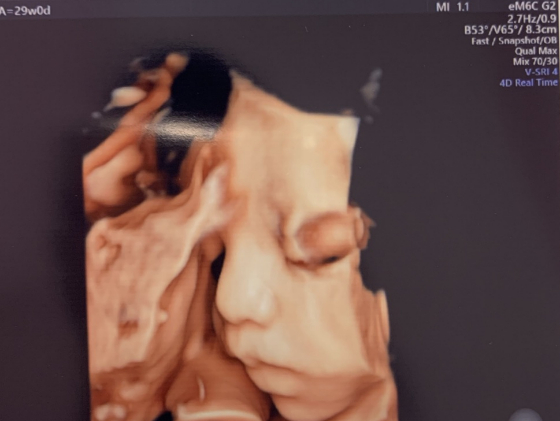

나무가 무럭무럭 자랐다. 점 하나만 하던 아가가 심장 소릴 들려주었다. 컴컴한 초음파실에서 별안간 울음을 쏟았다. 아내는 심한 감기에 걸려 기침에 밤을 새우면서도, 약 한 번 안 먹고 나무를 지켰다. 그리 안전히 자랐다. 통통통, 발길질하고, 꿀렁하며 자세를 바꿀 때마다 함께 탄성을 질렀다. 딸꾹질하는 거 보라고 웃었다. 그리 만삭이 되었다.